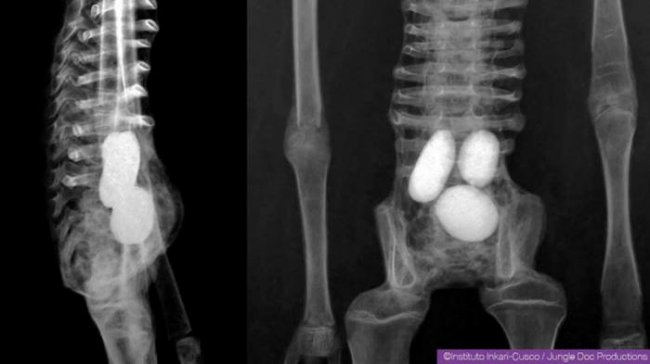

Рентген мумии «Жозефина» (Josefina)

Мумии отличаются друг от друга по своей анатомии. Тем более, что ДНК, судя по озвученной информации о результатах проведенных анализов, не во всех случаях настолько далека от ДНК человека. На «рептильность» (в нашем понимании), действительно, указывают некоторые признаки. По крайней мере, одно существо было яйцекладущим, и строение носа показывает, что вдыхаемый воздух не обогревался как у человека (теплокровного). Однако этого, на мой взгляд, мало для того, чтобы однозначно отнести этих существ к рептилоидам. Тем более, что они не относятся к одному и тому же биологическому виду. Это становится понятно как при простом визуальном осмотре, так и, например, при сравнении формы ступней и ладоней, ребер, других участков тел.